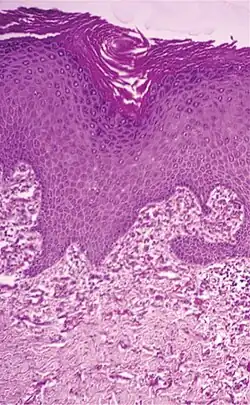

| Elastosis perforans serpiginosa | Degenerated elastic fibers and transepidermal perforating canals (arrow in image points at one of them)[13] |

|